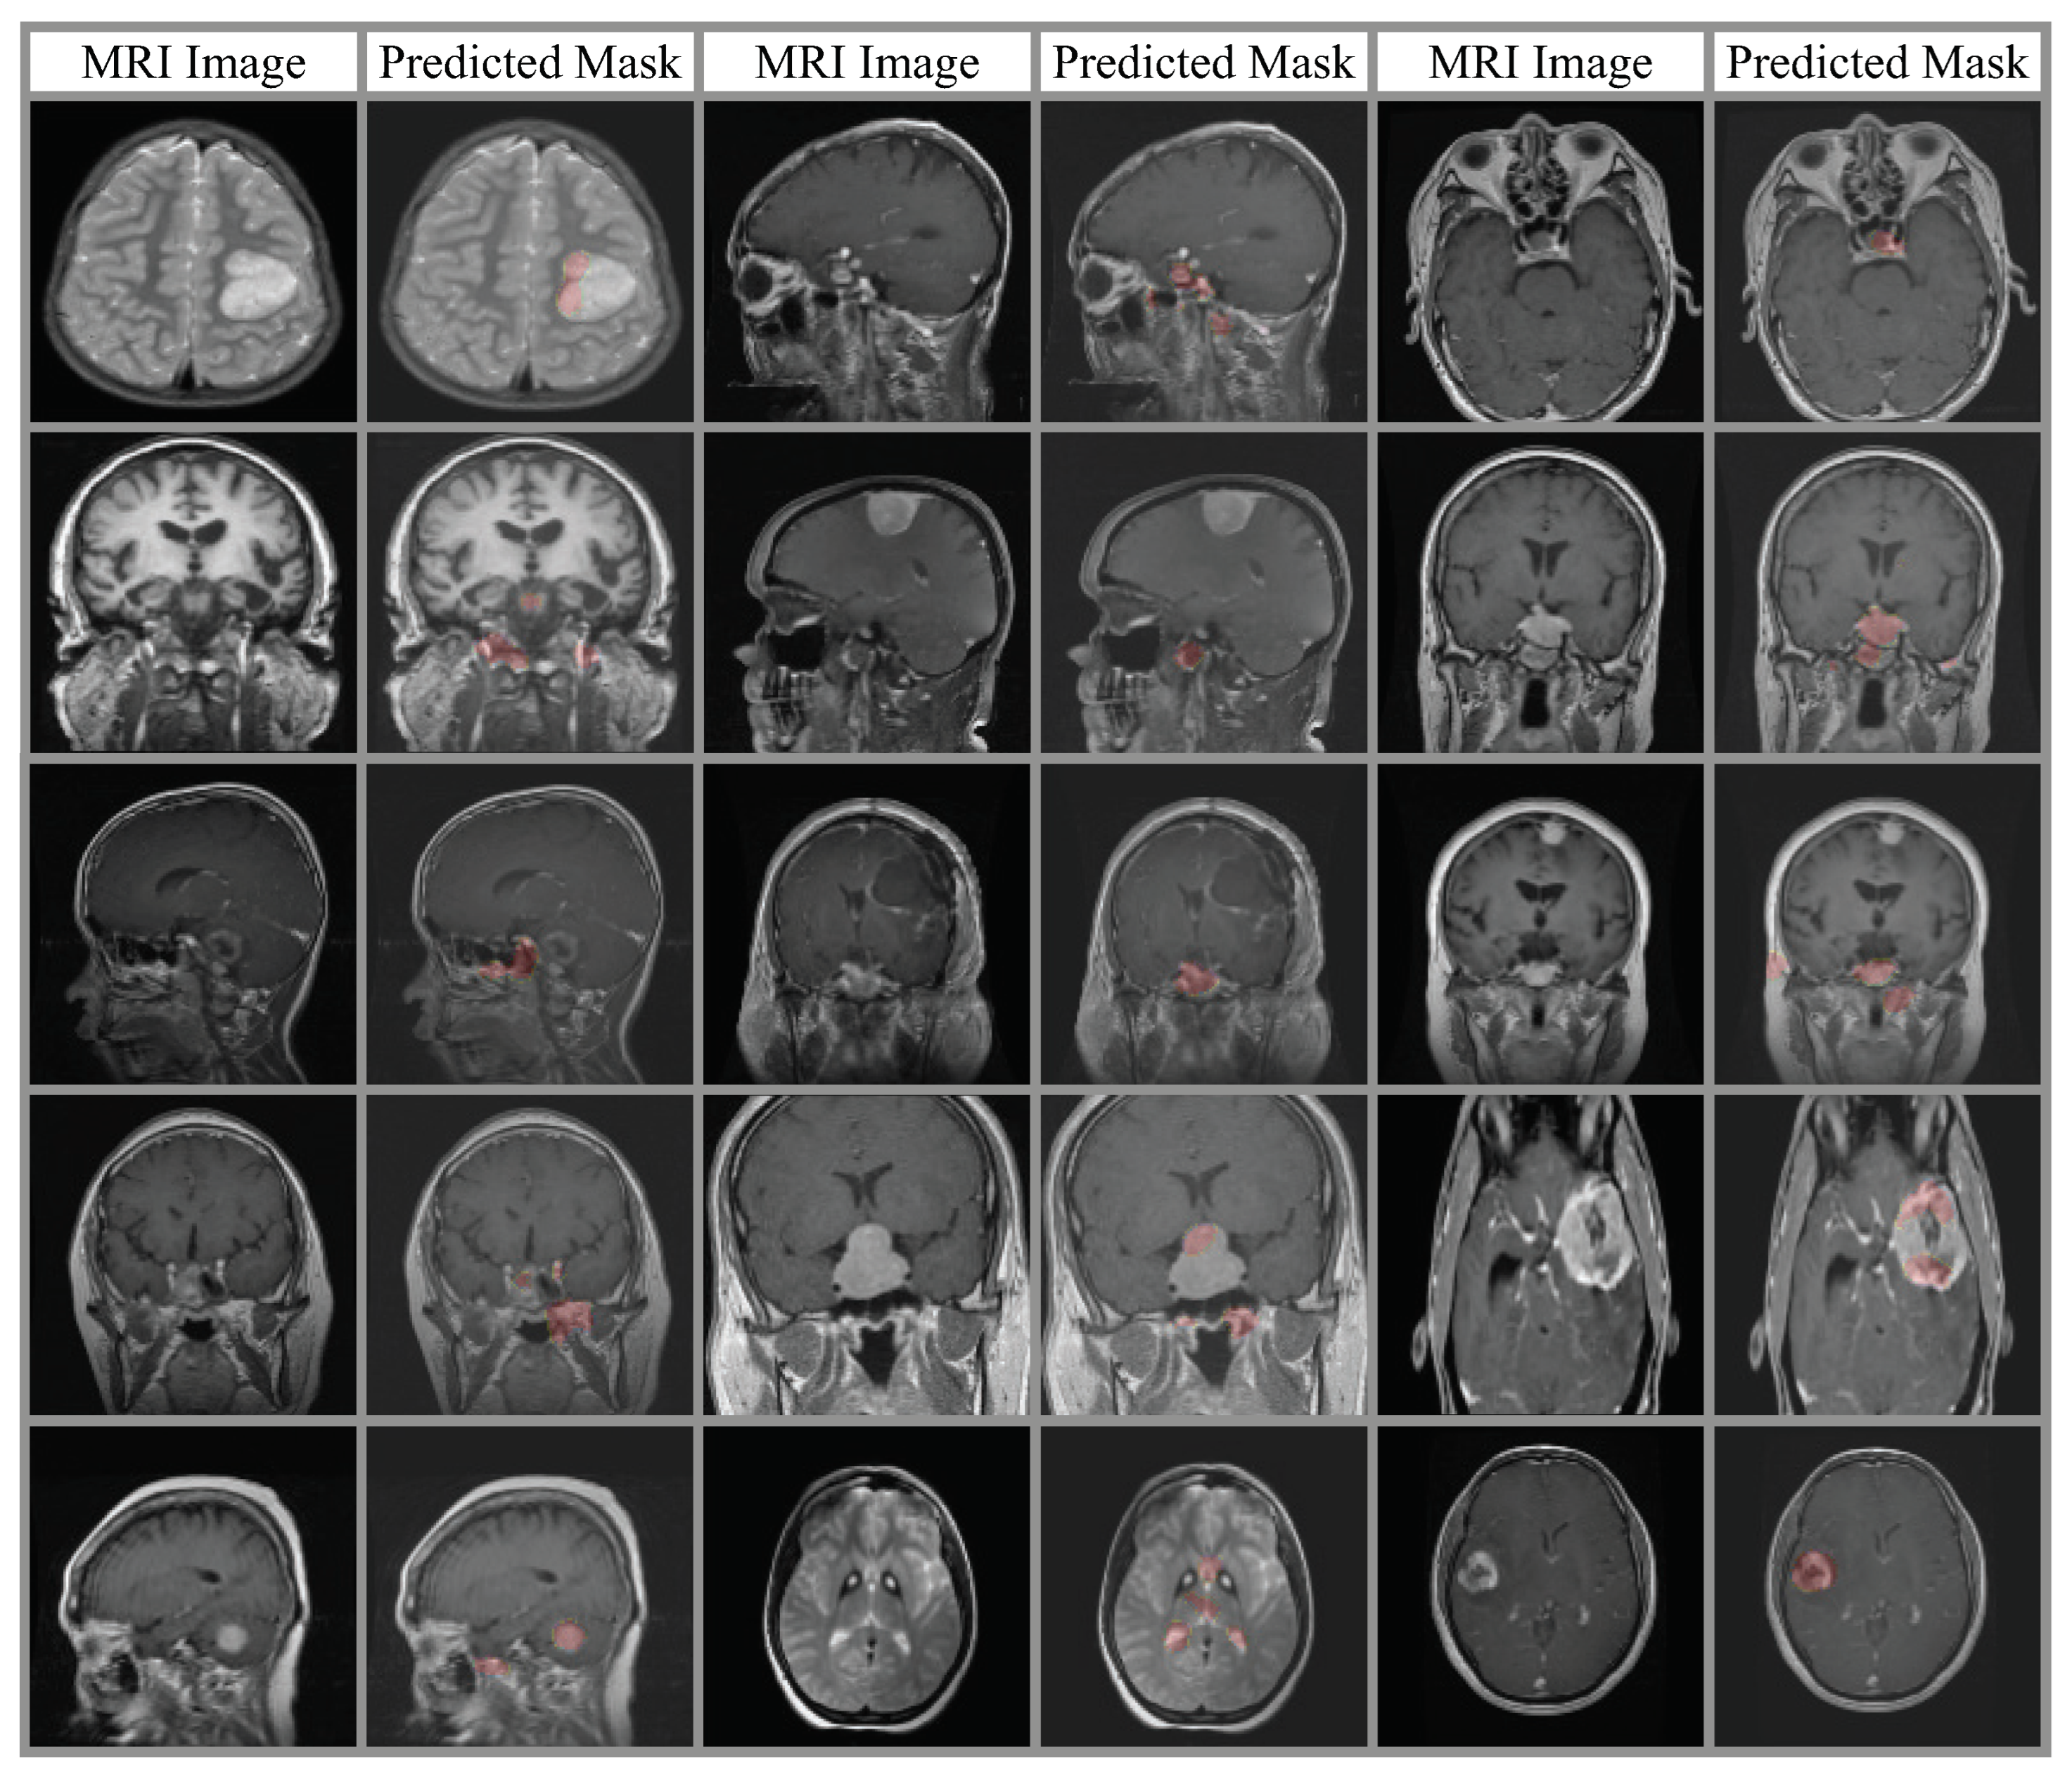

3.2. Spatial Attention Module

4. Experimental Results